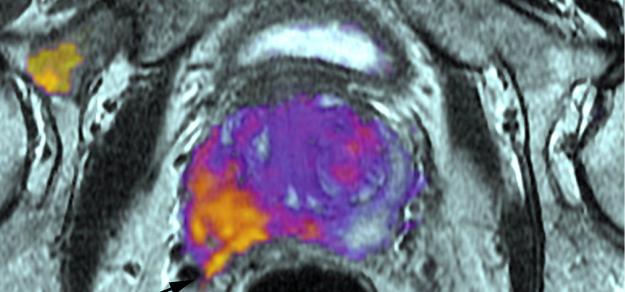

- Imágenes